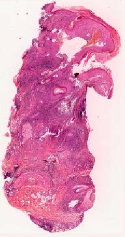

We demonstrate our WSI creation workflow on Leishmaniasis cases, as shown in Figures 1 and 4. An expert pathologist reviewed the cases and annotated granulomas as well as LD bodies on the stitched images and our generated images in Figure 4. To show generalizability of our approach, we also show results on core biopsies of breast, duodenum, stomach, liver, and lymph nodes (Figure 5).

| Breast | Duodenum | stomach | liver | lymph node | |||||

Curated dataset. Skin biopsies from 12 patients diagnosed with cutaneous leishmaniasis (spanning the disease differentiation spectrum) were acquired from Agha Khan University with Internal Review Board approval # 2024-9038-28175. Six of these biopsies, stained with hematoxylin & eosin (H&E), were scanned using Huron’s TissueScope digital scanner at 40X. A cheap-yet-clinical grade ($200) microscope (BS-2020MD Digital Microscope from BestScope International Limited, China) with a built-in digital 1.3 megapixel CMOS USB camera and 1W 5-LED illumination with Halogen Lamp 6V/20W was then used to capture videos for all 12 skin biopsies at 10X resolution. To show generalizability of our whole-slide image creation workflow for other common pathologies beyond cutaneous leishmaniasis, we also acquired videos for core biopsies of breast, liver, duodenum, stomach, and lymph node.